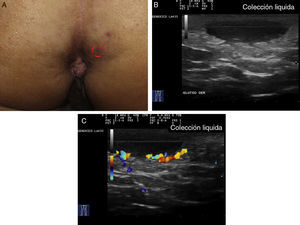

Criterios ecográficos de las lesiones elementales de la hidradenitis supurativaLos principales hallazgos ecográficos de la HS incluyen una alteración difusa del patrón dérmico, un engrosamiento dérmico, la presencia de pseudoquistes dérmicos, el engrosamiento del folículo piloso y la detección de colecciones fluidas y de tractos fistulosos (figs. 3–5)83.

Hidradenitis supurativa. A. Lesión alargada eritematosa que ocupa la axila derecha. En rojo, el área clínicamente afecta. En azul, el área ecográficamente afecta. B. Imagen ecográfica que muestra la existencia de un trayecto fistuloso subyacente. C. La función doppler muestra una actividad inflamatoria leve.

A continuación se produciría una alteración del patrón dérmico, inicialmente perifolicular y posteriormente difuso, con la presencia de un engrosamiento dérmico, que refleja el marcado proceso inflamatorio subyacente principalmente provocado por diferentes mediadores de la inmunidad innata. Así, la mayor o menor hipoecogenicidad y la extensión de la misma nos puede orientar hacia el grado de inflamación subyacente que presenta la enfermedad (figs. 3–5)83.

En aquellos casos con elevada carga inflamatoria aparecerían los denominados nódulos pseudoquísticos dérmicos (fig. 3 A y B), que ecográficamente se caracterizan por estructuras nodulares redondeadas u ovaladas hipo o anecoicas. El siguiente paso sería la aparición de colecciones fluidas que se caracterizan en la ecografía por depósitos fluidos hipo o anecoicos en la dermis o en la hipodermis conectados habitualmente a la base del folículo piloso alterado (fig. 4 A-C).